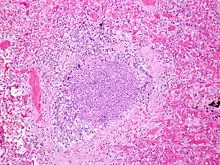

.jpg.webp)

The term usually refers to acute viral bronchiolitis, a common disease in infancy. This is most commonly caused by respiratory syncytial virus[11] (RSV, also known as human pneumovirus). Other agents that cause this illness include human metapneumovirus, influenza, parainfluenza, coronavirus, adenovirus, rhinovirus and mycoplasma.[12][13]